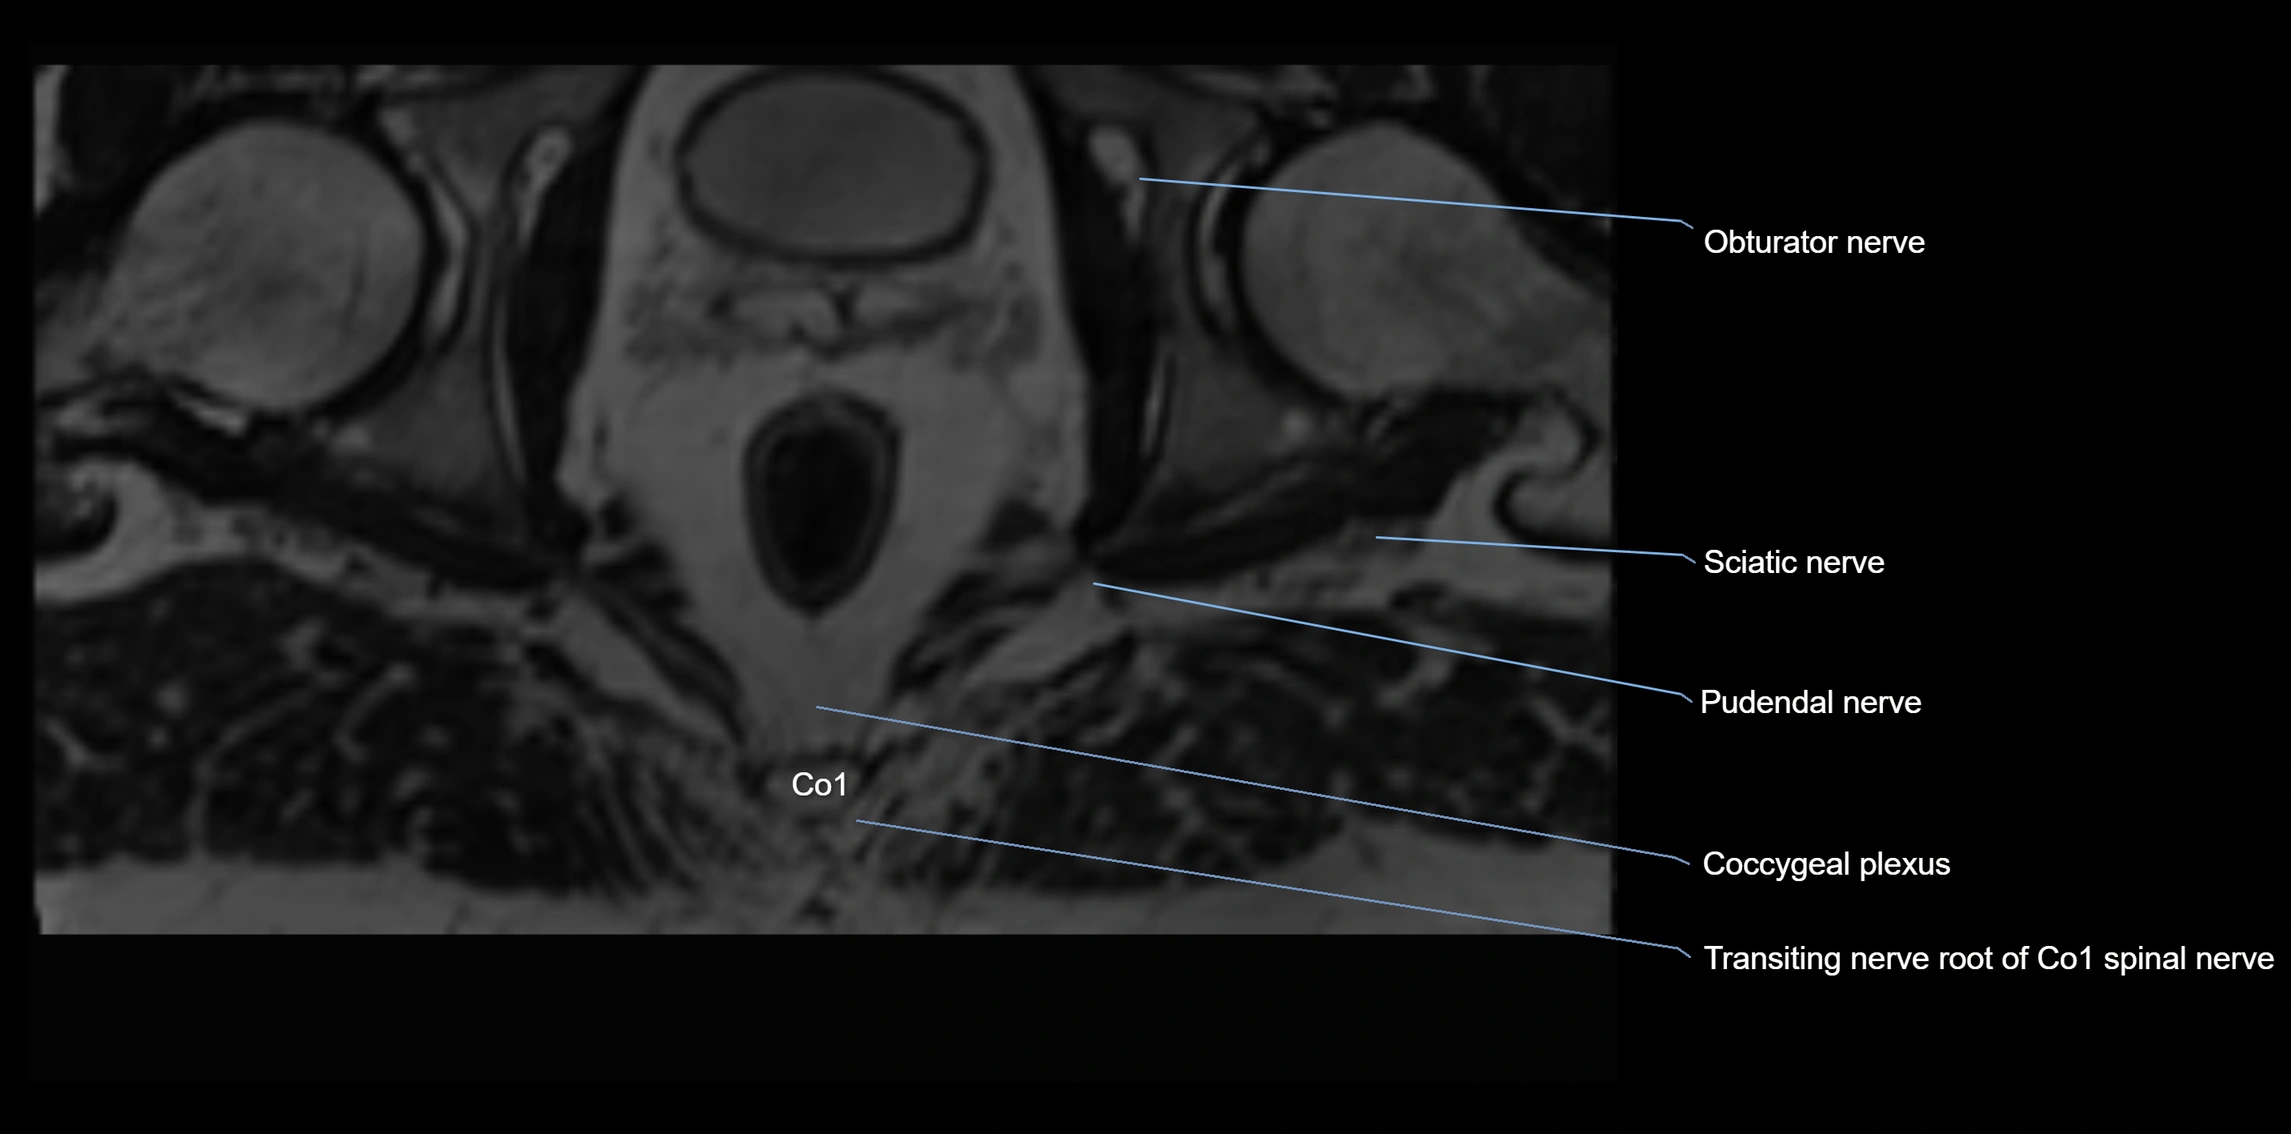

Anococcygeal nerve

The anococcygeal nerve is a small sensory nerve derived from the coccygeal plexus, which itself is formed by the ventral rami of S4, S5, and the coccygeal nerve (Co1). Although tiny, this nerve plays an important role in supplying the skin of the coccyx and the area between the anus and coccyx. It passes through the sacrotuberous ligament and runs in the midline behind the coccyx.

Despite its small size, the anococcygeal nerve is clinically important because of its involvement in coccygodynia (coccyx pain) and perineal pain syndromes.

MRI image

image